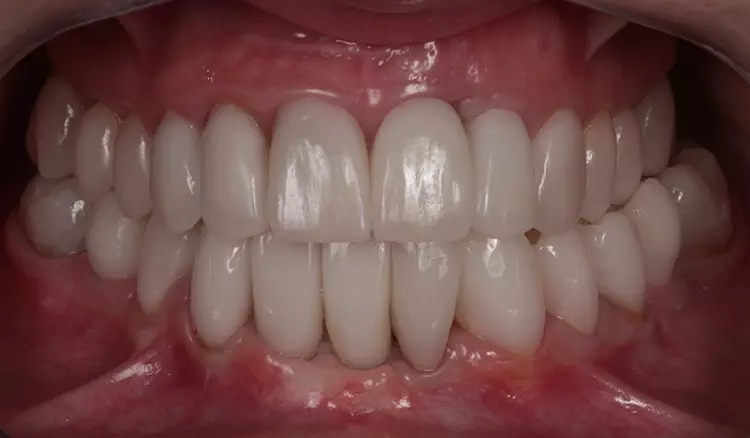

Der Unterkiefer „arbeitet“ nach Abschluss der Rekonstruktion „interferenzfreier“ und „muskulär koordinierter“ als je zuvor, was für die Kaumuskulatur weniger Kraftaufwand (keine Vermeidungs- und Ausweichbewegungen) und mehr Effizienz (verbesserte Okklusion und Artikulation, Abb. 15 bis 17) bedeutet. Dies ist der Therapieplanung (im Sinne eines „Backward-Planning) und deren gezielter Umsetzung und somit hoher Vorhersagbarkeit für eine langfristige Prognose der Rekonstruktion zuzusprechen. Im Molarenbereich zeigen sich noch dynamische Kontakte, insbesondere bei parafunktioneller Aktivität (Abb. 18), die sich auch im Erscheinungsbild der Condylografie-Kurven widerspiegeln.

Aufgrund der klinischen Beschwerdefreiheit und auch der Tatsache, dass Heilungs- und Umbauvorgänge im Gelenk noch stattfinden können, soll vorerst noch 6 bis12 Monate bei regelmäßiger klinischer Nachkontrolle abgewartet werden. Die Patientin ist subjektiv beschwerdefrei (keine Anzeichen einer Dekompensation in der klinischen Funktionsanalyse). Zudem äußert sie keine Druckdolenz der Kaumuskulatur und/oder der Gelenke [22,23] (Abb. 19 bis 22).